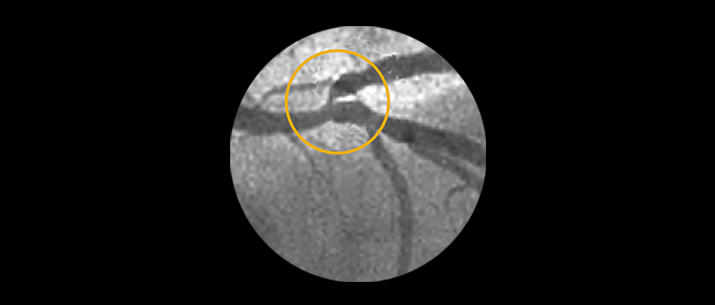

Ostial and bifurcation lesions represent nearly 40% of complex PCI’s.1